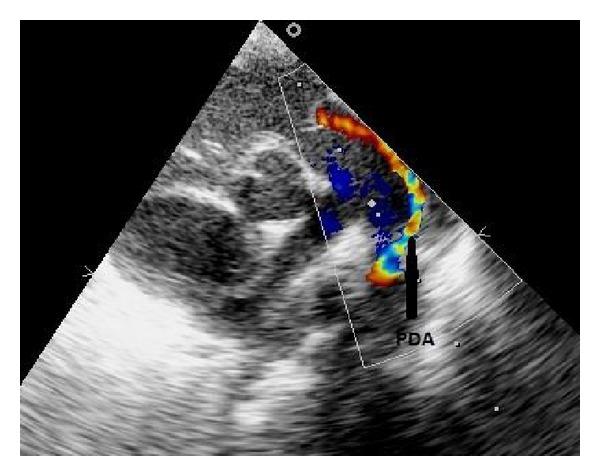

Congenital sternal cleft is a rare abnormality resulting from fusion failure of sternum. It occurs in isolation or along with defects of abdominal wall, diaphragm, pericardium, and heart. Early surgical correction is required to protect the underlying structures for risk of cardiac compression. Here we report a case of 20-day female child presenting with congenital sternal cleft associated with multiple congenital heart disease and left-sided superior vena cava. She was operated by the cardiothoracic surgical team successfully and is doing well on followup. We discuss this rare case, imaging studies, and surgical strategy.

先天性胸骨裂是一种由于胸骨融合失败导致的罕见畸形。它可单独发生,也可伴有腹壁、膈肌、心包和心脏的缺陷。需要早期手术矫正以保护潜在结构,防止心脏受压风险。在此,我们报告一例20天大的女婴,患有先天性胸骨裂并伴有多种先天性心脏病和左侧上腔静脉。她由心胸外科团队成功进行了手术,随访情况良好。我们讨论了这个罕见病例、影像学检查和手术策略。